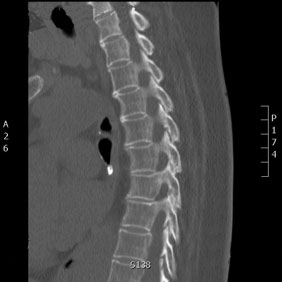

Tomografía computarizada Columna

< Volver a "Tomografía Computarizada (TC) con Inteligencia artificial"Con esta prueba valoraremos la patología de las vertebras, fracturas, hernias, protusiones discales,…